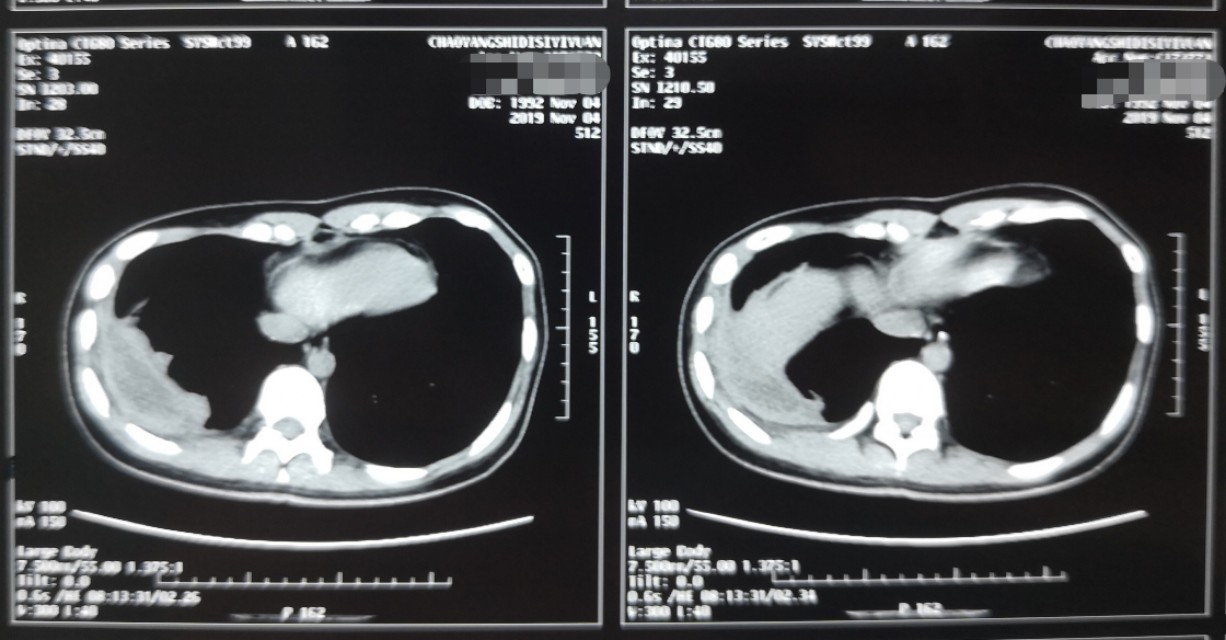

一位花季女孩不幸遭受慢性脓*摧胸**残,保守治疗右侧脓腔不能消灭,胸廓塌陷,开胸手术实在难以接受������